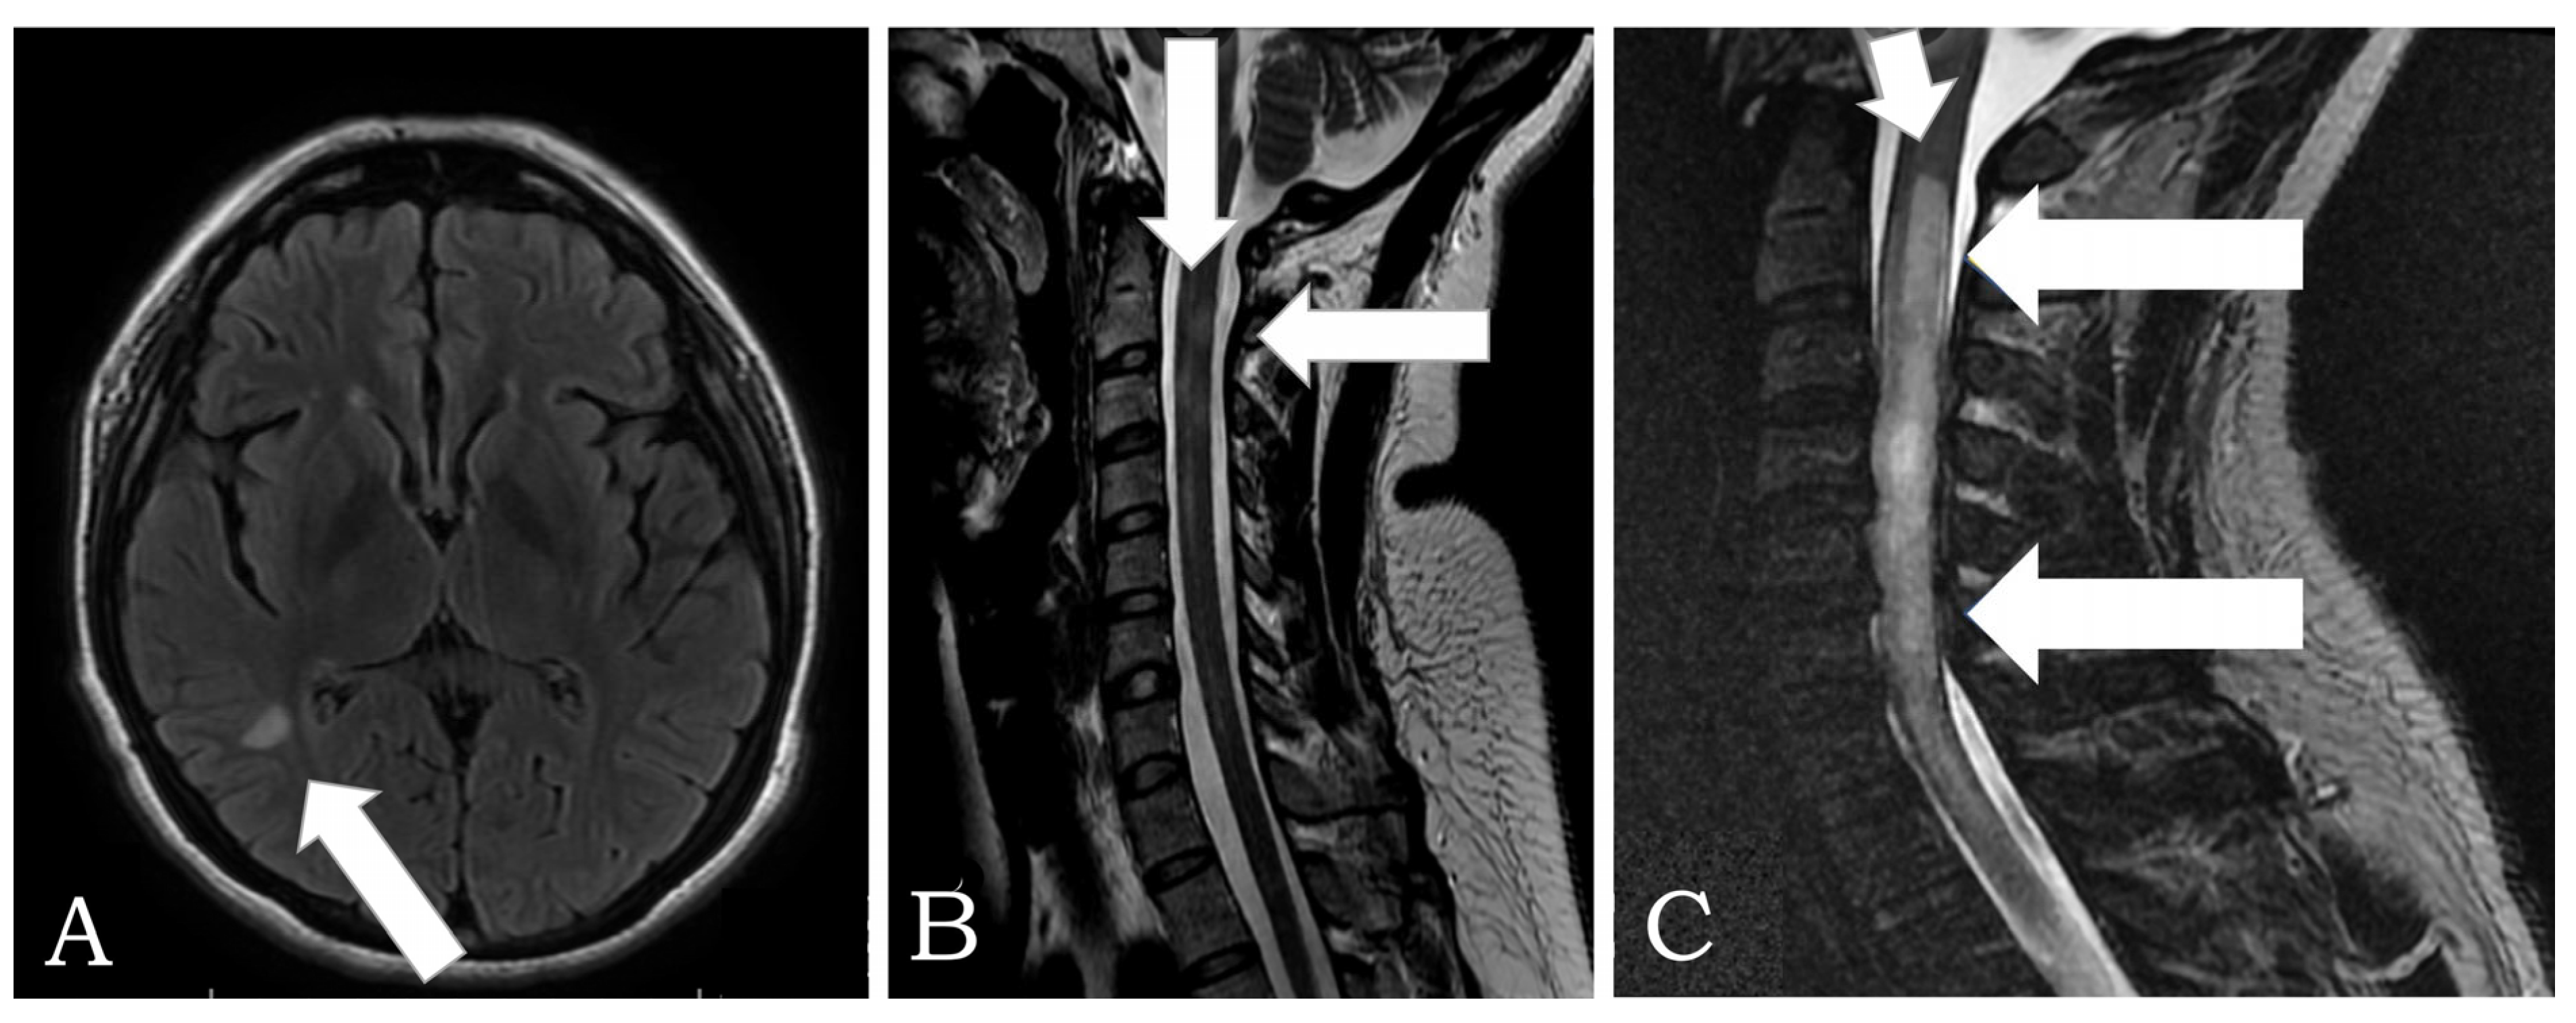

| Neuromyelitis Optica Spectrum Disorder | 2 | F: 2 | 37± 15.6 | None | AQP-4: 2 Positive Anti-NMDAr: Negative * Anti- GABA: Negative * Anti-GADAb: Negative * | 2nd: 2 | 7 (5–10) |